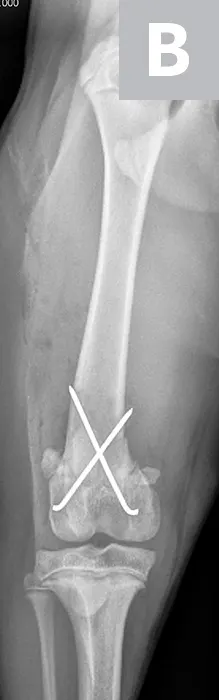

Maggie was managed overnight with analgesia (ie, hydromorphone [0.05 mg/kg IV q4-6h]) and nursing care. The following morning, Maggie was placed under general anesthesia and given a morphine epidural, and surgical fixation of the fracture was performed through a craniolateral approach to the stifle. The distal femoral physis is W-shaped and has inherent stability when reduced; however, additional stabilization is required to provide adequate resistance to the forces applied across the fracture and to allow for the stability needed for healing. Two smooth pins were placed obliquely across the fracture site (Figure 2). The pins should cross proximal to the fracture site to provide maximal repair stability.7

Figure 2

Lateral (A) and craniocaudal (B) radiographs of the femur immediately after open reduction and internal fixation with 2 cross pins. The pins cross proximal to the fracture site, which is important for stability of the repair.